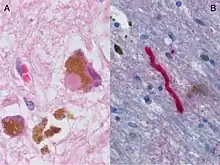

Histological brain sample of the Substantia Nigra in Parkinson's disease, showing the presence of Lewy bodies and other signs of neurodegeneration.

Parkinson's disease (PD) is a neurodegenerative disease resulting from the apoptosis of dopaminergic neurons in the central nervous system, especially the substantia nigra, as well as heightened response to the excitatory neurotransmitter, glutamate (i.e., excitotoxicity).[12] While the most obvious symptoms are related to motor skills, prolonged progression of the disease can lead to cognitive and behavioral problems as well as dementia. Although the mechanism of apoptosis in the brain is not entirely clear, speculation associates cell death with abnormal accumulation of ubiquitinated proteins in cell occlusions known as Lewy bodies, as well as hyperstimulation of neuronal NMDA receptors with excessive glutamate neurotransmitter via the aforementioned pathway.[12] Like Alzheimer's, Parkinson's Disease lacks a cure. Therefore, in addition to lifestyle changes and surgery, the goal of pharmaceutical drugs used in the treatment of PD patients is to control symptoms and limit, when possible, the progression of the disease. Levodopa (L-DOPA), the most widely used treatment of PD, is converted to dopamine in the body and helps to relieve the effect of decreased dopaminergic neurons in the central nervous system. Other dopamine agonists have been administered to patients in an effort to mimic dopamine’s effect at excitatory synapses, binding its receptors and causing the desired postsynaptic response.[13]